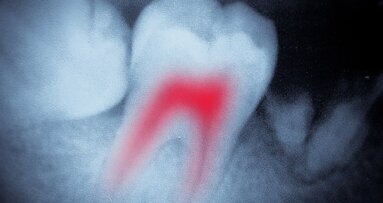

The preparation of the access cavity can be performed directly with Erbium lasers, which can ablate enamel and dentine. In this case, the use of a short tip is recommended (from 4 to 6mm), with diameters between 600 and 800µm, made of quartz to allow the use of higher energy and power. The importance of this technique should not be underestimated. Owing to its affinity to tissues richest in water (pulp and carious tissue), the laser allows for a minimally invasive access (because it is selective) into the pulp chamber and, at the same time, allows for the decontamination and removal of bacterial debris and pulp tissue. Access to the canal orifices can be accomplished effectively after the number of bacteria has been minimised, thereby avoiding the transposition of bacteria, toxins and debris in the apical direction during the procedure. Chen et al. demonstrated that bacteria are killed during cavity preparation up to a depth of 300 to 400µm below the radiated surface.20 Moreover, Erbium lasers are useful in the removal of pulp stones and in the search for calcified canals.

The preparation of the canals with NiTi instruments is still the gold standard in endodontics today. In fact, despite the recognised ablative effect of Erbium lasers (2,780 and 2,940nm) on hard tissue, their effectiveness in the preparation of root canals appears to be limited at the moment and does not correspond to the endodontic standards reached with NiTi technology.21–23 However, the Erbium,Chromium: YSGG (Er,Cr:YSGG) and the Erbium:YAG (Er:YAG) lasers have received FDA approval for cleaning, shaping and enlarging canals. A few studies have reported positive results for the efficacy of these systems in shaping and enlarging radicular canals. Shoji et al. used an Er:YAG laser system with a conical tip with 80% lateral emission and 20% emission at the tip to enlarge and clean the canals using 10 to 40mJ energy at 10Hz, obtaining cleaner dentinal surfaces compared with traditional rotary techniques.24

In a preliminary study on the effects of the Er:YAG laser equipped with a microprobe with radial emission of 200 to 400µm, Kesler et al. found the laser to have good capability for enlarging and shaping in a faster and improved manner compared with the traditional method. The SEM observations demonstrated a uniformly cleaned dentinal surface at the apex of the coronal portion, with an absence of pulp residue and well-cleaned dentinal tubules.25 Chen presented clinical studies prepared entirely with the Er,Cr:YSGG laser, the first laser to obtain the FDA patent for the entire endodontic procedure (enlarging, clearing and decontaminating), using tips of 400, 320 and 200µm in succession and the crown-down technique at 1.5W and 20Hz (with air/water spray 35/25%).26,27

Stabholz et al. presented positive results of treatment performed entirely using a Er:YAG laser and endodontic lateral emission microprobes.28,29 Ali et al., Matsuoka et al. and Jahan et al. used the Er,Cr:YSGG laser to prepare straight and curved canals, but in these cases, the results of the experimental group were worse than those of the control group. Using the Er,Cr:YSGG laser with 200 to 320µm tips at 2W and 20Hz on straight and curved canals, they concluded that the laser radiation is able to prepare straight and curved (less than 10°) canals, while more severely curved canals demonstrated side-effects, such as perforations, burns and canal transportation.21–23 Inamoto et al. investigated the cutting ability and the morphological effects of radiation of the Er:YAG laser in vitro, using 30mJ at 10 and 25Hz with a velocity of extraction of the fibre at 1 and 2mm/seconds, again with positive results.30 Minas et al. reported positive results using the Er,Cr:YSGG laser at 1.5, 1.75 and 2.0W and 20Hz, with water spray.31

The surfaces prepared with the Erbium laser are well cleaned and without smear layer, but often contain ledges, irregularities and charring with the risk of perforations or apical transportation. In effect, canal shaping performed by Erbium laser is still a complicated procedure today that can be performed only in large and straight canals, without any particular advantages.